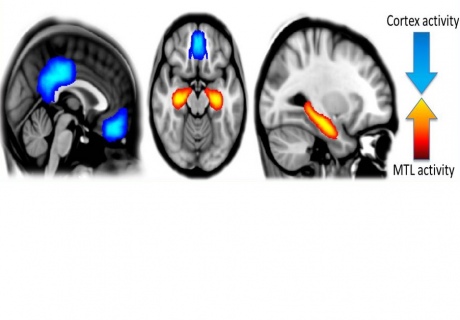

Actividad cerebral bajo el efecto de la psilocibina, con una reducción (en azul) de la actividad en las regiones cerebrales evolutivamente avanzadas, y una reducción (en naranja) en los centros de memoria y emoción. Fuente: Imperial College de Londres.

Reveló que, bajo los efectos de la psilocibina, aumentaba la actividad en la red más primitiva del cerebro, que está vinculada al pensamiento emocional.

Esta activación pronunciada implicó a varias regiones de dicha red al mismo tiempo, como el hipocampo (asociado a la memoria y la emoción) o la corteza cingulada anterior (relacionada con los estados de excitación).

Por otra parte, en los voluntarios sometidos al estudio se detectó una actividad más inconexa y descoordinada en la red cerebral vinculada al pensamiento avanzado, que hace posible, por ejemplo, que tengamos autoconciencia.